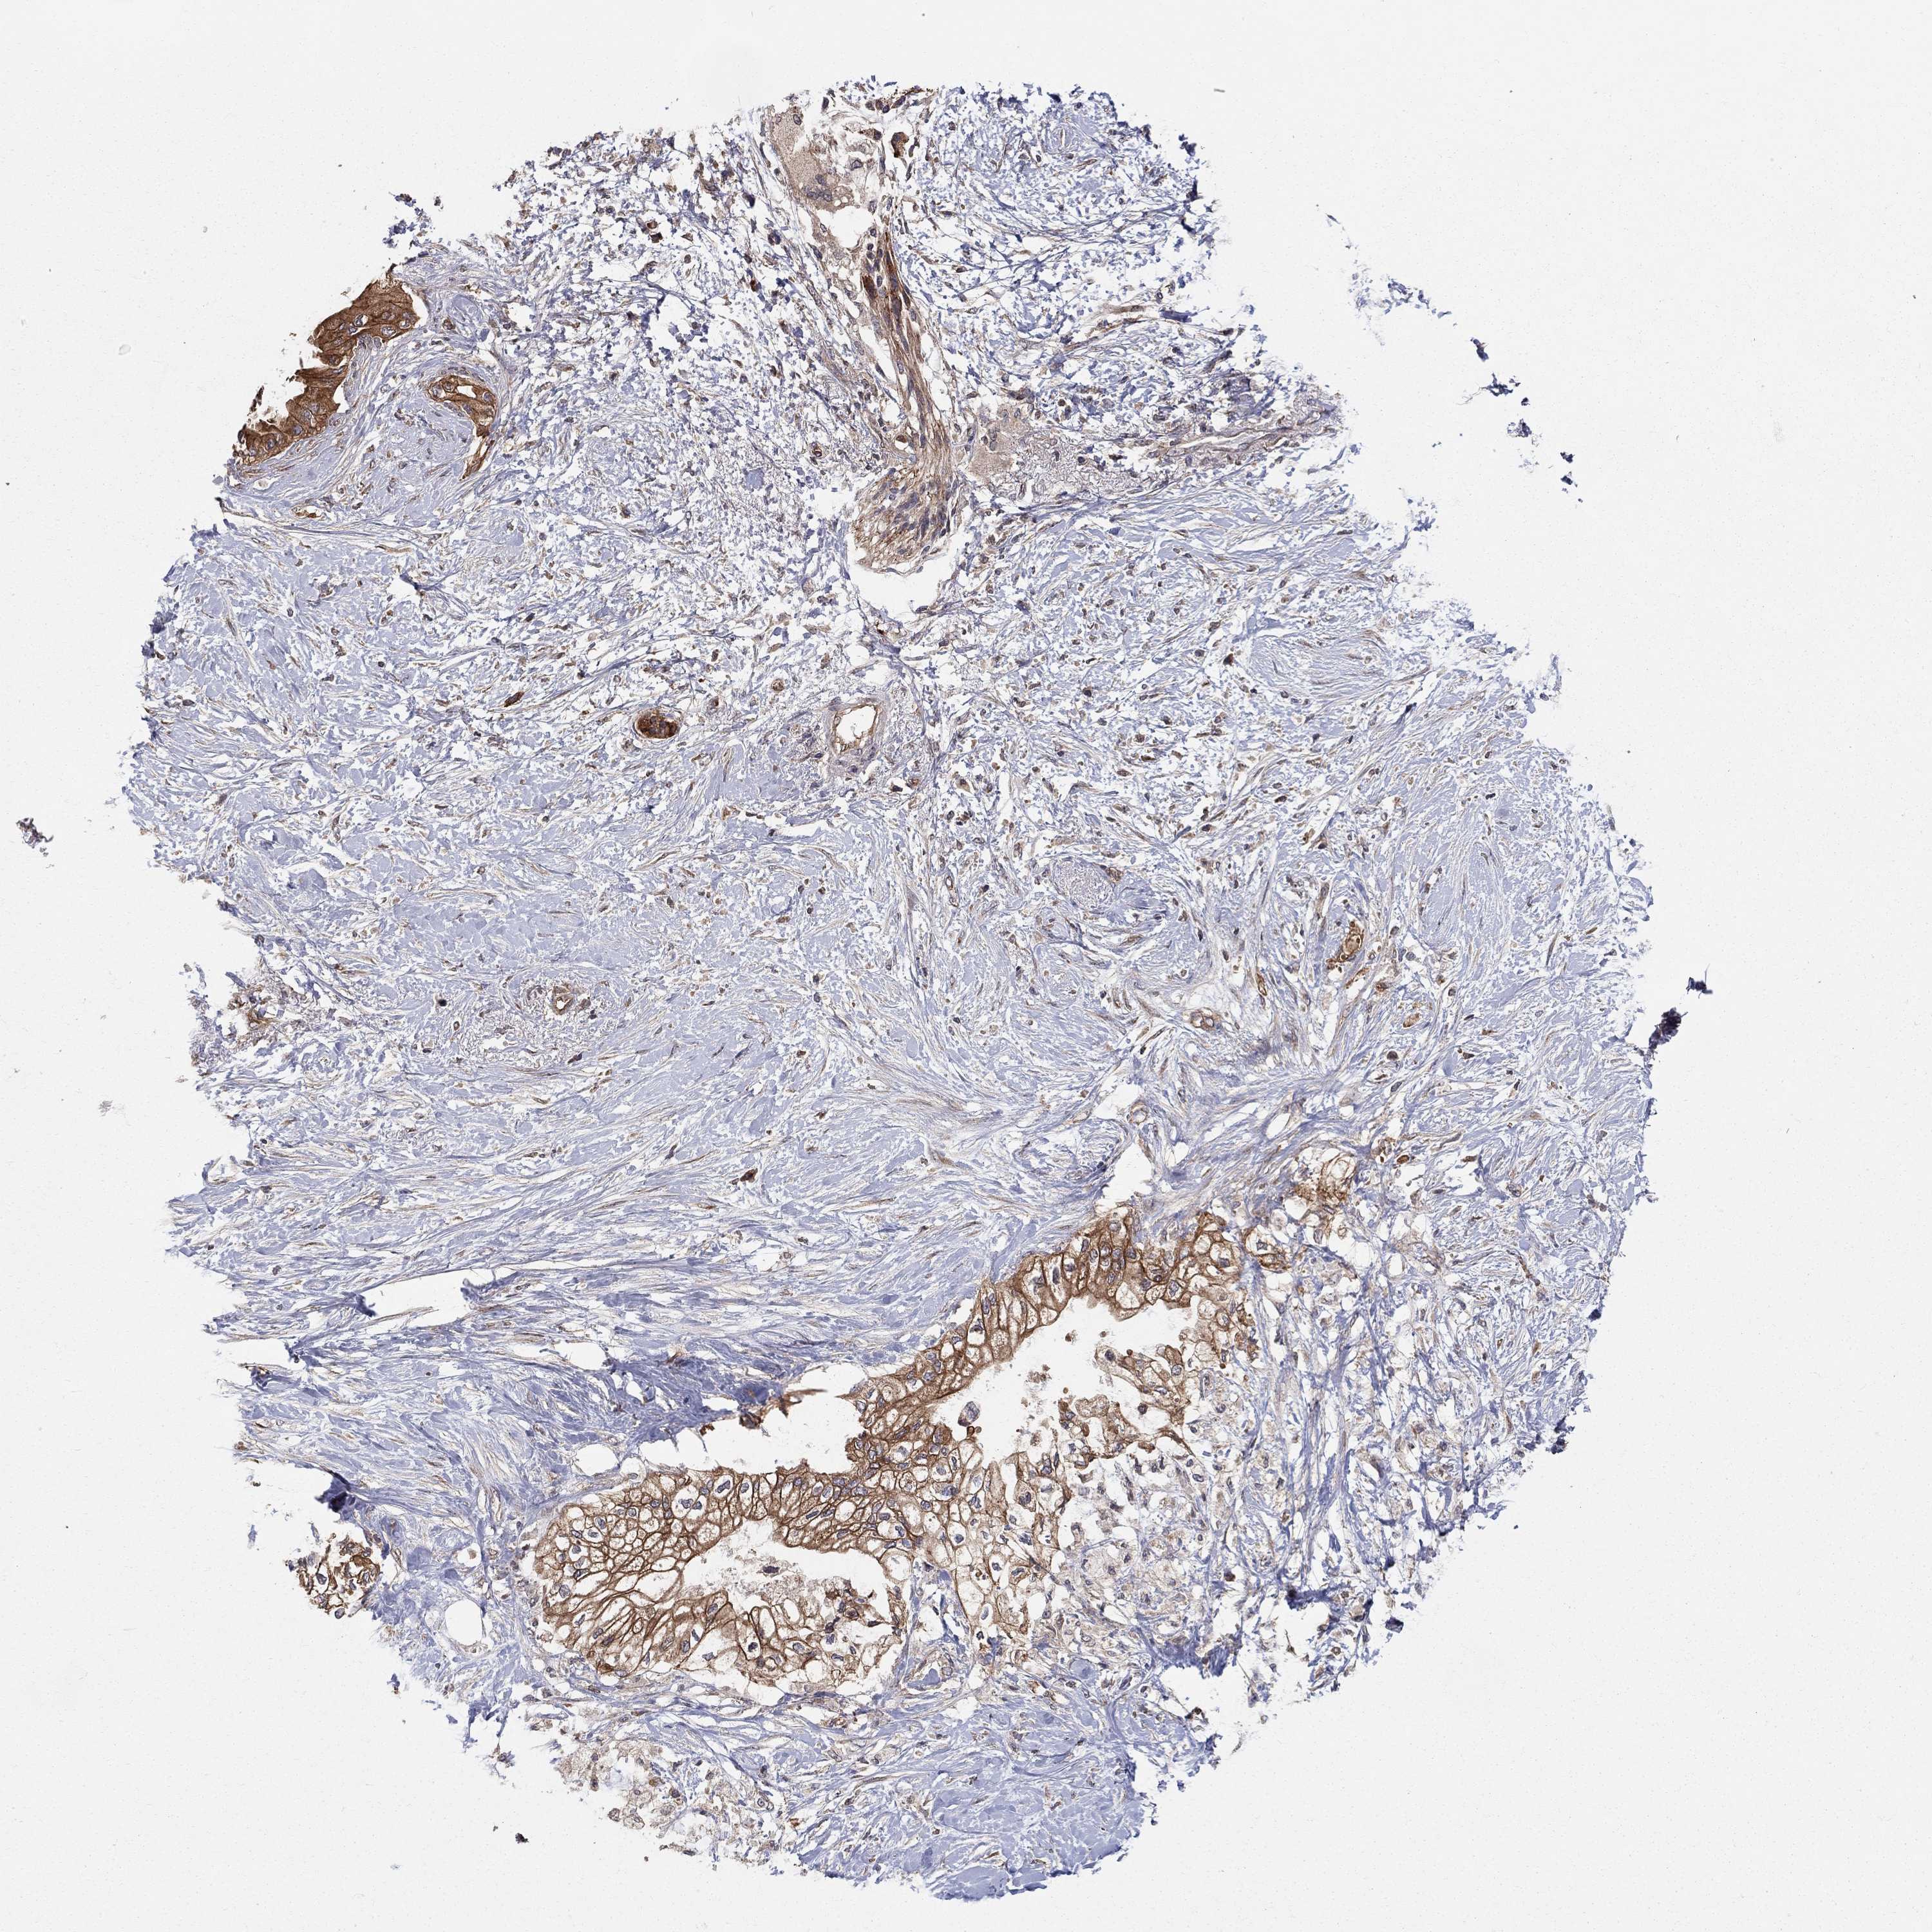

PANCREATIC CANCER - Protein expressioni

A mouse-over function shows sample information and annotation data. Click on an image to view it in a full screen mode. Samples can be filtered based on level of antibody staining by selecting one or several of the following categories: high, medium, low and not detected. The assay and annotation is described here.

Note that samples used for immunohistochemistry by the Human Protein Atlas do not correspond to samples in the TCGA dataset.

Antibody stainingi

Antibody staining in the annotated cell types in the current human tissue is reported as not detected, low, medium, or high, based on conventional immunohistochemistry profiling in selected tissues. This score is based on the combination of the staining intensity and fraction of stained cells.

Each image is clickable and will lead to virtual microscopy that enables deeper exploration of all samples and also displays staining intensity scores, fraction scores and subcellular localization as well as patient and tissue information for each sample.

Antibody HPA041114

Antibody HPA063757

Staining

High

Medium

Low

Not detected

Intensity

Strong

Moderate

Weak

Negative

Quantity

>75%

75%-25%

<25%

None

Location

Nuclear

Cytoplasmic/membranous

Cytoplasmic/membranous,nuclear

Adenocarcinoma, NOS